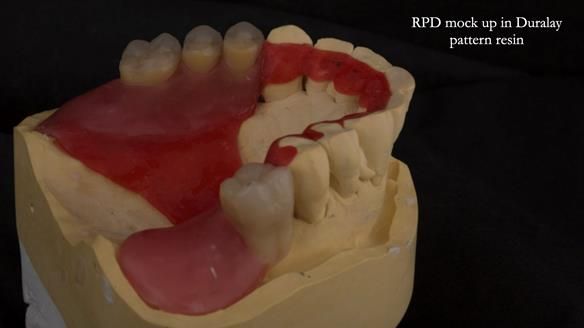

The upper jaw

In the upper arch:

- a failing upper left tooth supporting a bridge was removed

- an implant-supported bridge on the upper right was dismantled

A metal-based upper RPD was made,

with metal backings incorporated to future-proof the design

should further teeth fail.